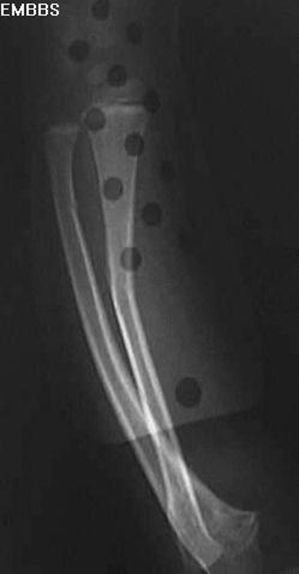

前臂青枝骨折

疼痛科怎么理疗疼痛科医生、康复理疗科医生、针刀针灸医生应掌握的常见骨科疾病X光片_https://www.jmylbn.com_新闻资讯_第18张